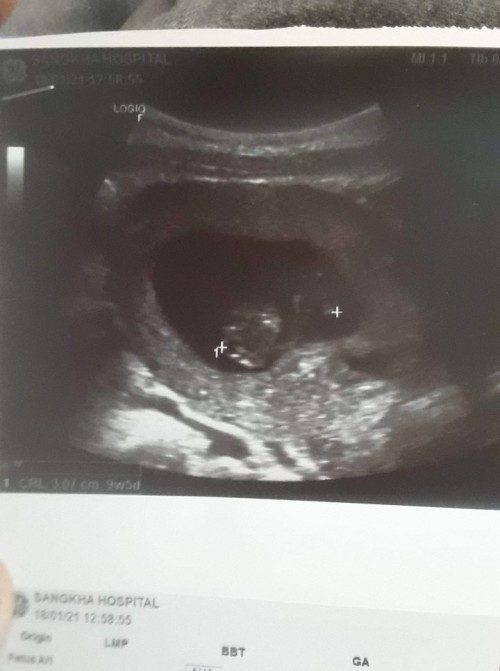

แม่! 🤰💖อวดรูปอัลตร้าซาวด์กัน

โชว์รูปแรกของเบบี้กันหน่อยน้า เพศหญิง👧หรือชาย🧑เอ่ยยย 😍🥰💜 17/09/2563